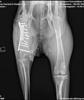

menschenorientiert, freundlich, anhänglich, aufmerksam, wachsam, gelehrig, zunächst misstrauisch bei fremden PersonenDoris ist eine vermutlich Anfang 2022 geborene, kastrierte Zentralasiatische Schäferhündin, die ausgesetzt gefunden und in das Tierheim unserer ungarischen Partnerorganisation gebracht wurde. Dort stellte sich heraus, dass sie einen schweren Unfall gehabt haben muss, denn sie hat rechts eine nicht versorgte und schlecht zusammengewachsene Oberschenkelfraktur.

Im Januar durfte Doris zu einer liebevollen Pflegestelle nach Österreich ziehen und hat seitdem die dringend benötigte Operation zur Stabilisierung des Knochens erhalten. Dank der großartigen Versorgung bei den Fachtierärzten Althangrund konnten wir die Kosten für diese lebensverändernde Operation von 8.000 Euro auf 5.000 Euro senken.

Die erste Operation verlief gut, und Doris’ Bein ist jetzt stabiler. Zur völligen Genesung benötigt sie nun jedoch eine Muskelansatz-OP, deren Kosten sich auf ca. € 2.300,– belaufen werden. 🥰 Dank eurer unglaublichen Unterstützung konnten wir die lebensrettende Operation finanzieren.